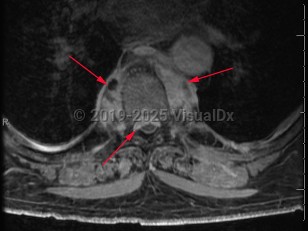

Paraspinal abscess

Paraspinal abscess is a collection of pus located around the spinal cord. This is usually seen as a complication of vertebral osteomyelitis and discitis (diskitis) but may be related to hematogenous seeding during bloodstream infection. Epidural catheters and injections may lead to direct inoculation of the epidural space. Frequently, the location of the abscess is in the epidural space.

Patients may have acute (develops over hours) or subacute (develops over weeks to months) back pain. Fever may or may not be present. As the abscess forms, patients typically have focal and severe back pain. As the size of the abscess increases, it may impinge on the spinal cord, leading to signs of spinal cord compression, including motor weakness and sensory deficits. Untreated, the patient's neurologic symptoms can worsen to the point of irreversible paralysis.

Diagnosis is typically made after the patient undergoes surgical drainage of the abscess. Infective material can be cultured to establish a diagnosis. Common laboratory findings include leukocytosis and elevation in inflammatory markers (sedimentation rate or C-reactive protein). Concomitant bloodstream infection may be present.